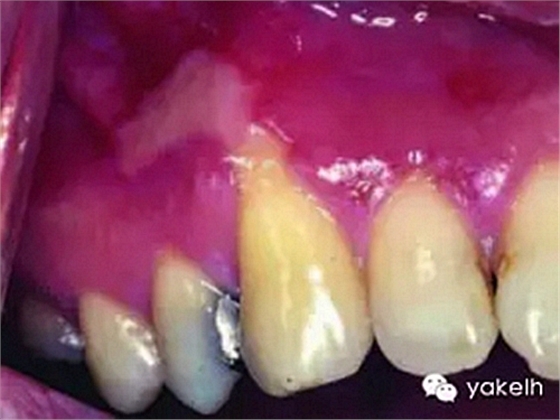

¤¤現(xiàn)在臨床使用的樹脂基類牙科材料的潛在危害性尚不確定,迄今的觀點是由于合成物的組成成分較多,包括一些未明確的物質(zhì),所以產(chǎn)品的生物相容性可能不同。但是由于這類材料的主要成分(BISGMA、TEGDMA、HEMA)和合成的過程是一樣的,因此包括正畸粘結(jié)材料在內(nèi)的樹脂基牙科材料的基本生物相容性是相似的。體外實驗顯示在樹脂聚合后不久,其中的成分就可以釋放到口腔中并達到一定濃度,引起口腔黏膜的刺激性反(圖10.7),這種反應(yīng)一般是短期的,釋放量隨著時間的延長而減少。有關(guān)這方面的病例報道是很少見的,從理論上而言黏膜的刺激反應(yīng)可能被忽視了,忽視的原因可能是反應(yīng)不重或者被誤診。迄今仍沒有文獻報道在粘結(jié)全口固定矯正器后,殘留物質(zhì)的釋放量,當(dāng)然研究的結(jié)果也不能直接應(yīng)用于臨床。雖然最終暴露于口內(nèi)的粘結(jié)材料相對較少,但是在粘結(jié)過程中患者所接觸的材料和底漆的總量是高于粘結(jié)單個或幾個修復(fù)體的量。而且正畸粘結(jié)劑中的樹脂含量顯著高于牙修復(fù)材料,后者含有60%~80%的無機填料用來改善材料的耐磨性?,F(xiàn)今粘結(jié)全口固定矯正器的正畸患者在治療中及治療后,到底有多少粘結(jié)材料被釋放到口內(nèi)還不知道。

圖10.7 13齦緣處復(fù)合樹脂修復(fù)24h后,鄰近局部出現(xiàn)刺激性黏膜反應(yīng)。